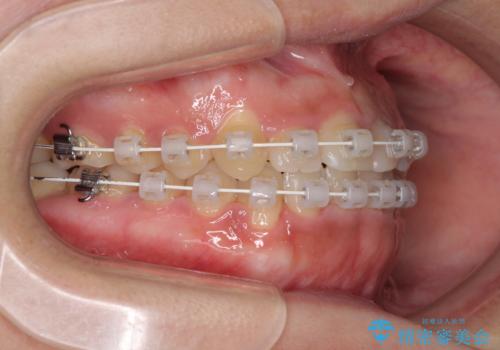

- 矯正装置

- 審美装置

インビザラインでの矯正治療も十分に対応可能でしたが、自己管理の煩わしさから、ワイヤー矯正を行うこととしました。